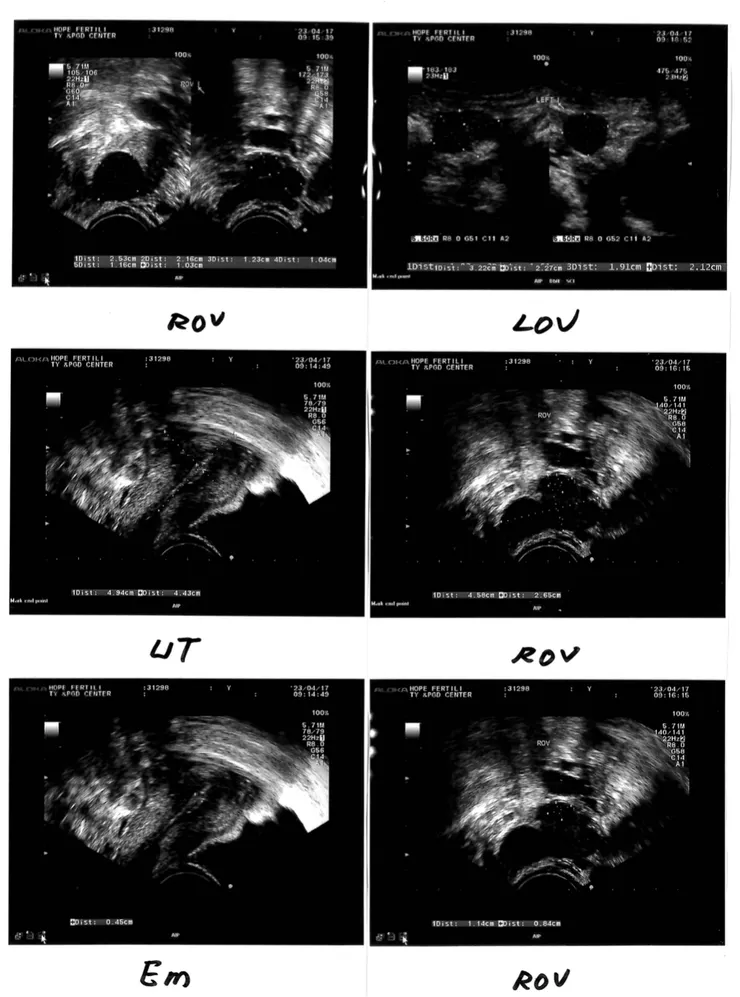

Molly有跟Dr. Vu談到我上次取卵,大的卵泡跟小的有落差,Dr. Vu開了美諾孕給我,他覺得美諾孕可以幫助小的卵泡長快一點。追蹤看起來,美諾孕的確有效。這次Day 2照的基礎卵泡是6顆,Day 7照的時候是9顆(有7顆大小差不多的、2顆小的)。雖然已經盡量拉齊,但後面那兩顆如果漲不起來,可能還是沒辦法。

分享這次祈新給我的陰超報告,有附上陰超照片很方便美國閱讀。另外,祈新是直接傳電子檔過來給我,轉傳給美國很方便。Molly說,他看我超音波的照片,卵泡長的很圓。我心裡面其實很納悶,難道還有人卵長的是其他形狀的嗎?!但後來我想想,我還真的有聽說其他同志取卵,有取出的卵長的是蘑菇狀或是栗子狀的,可能卵的長相還是會有差異。